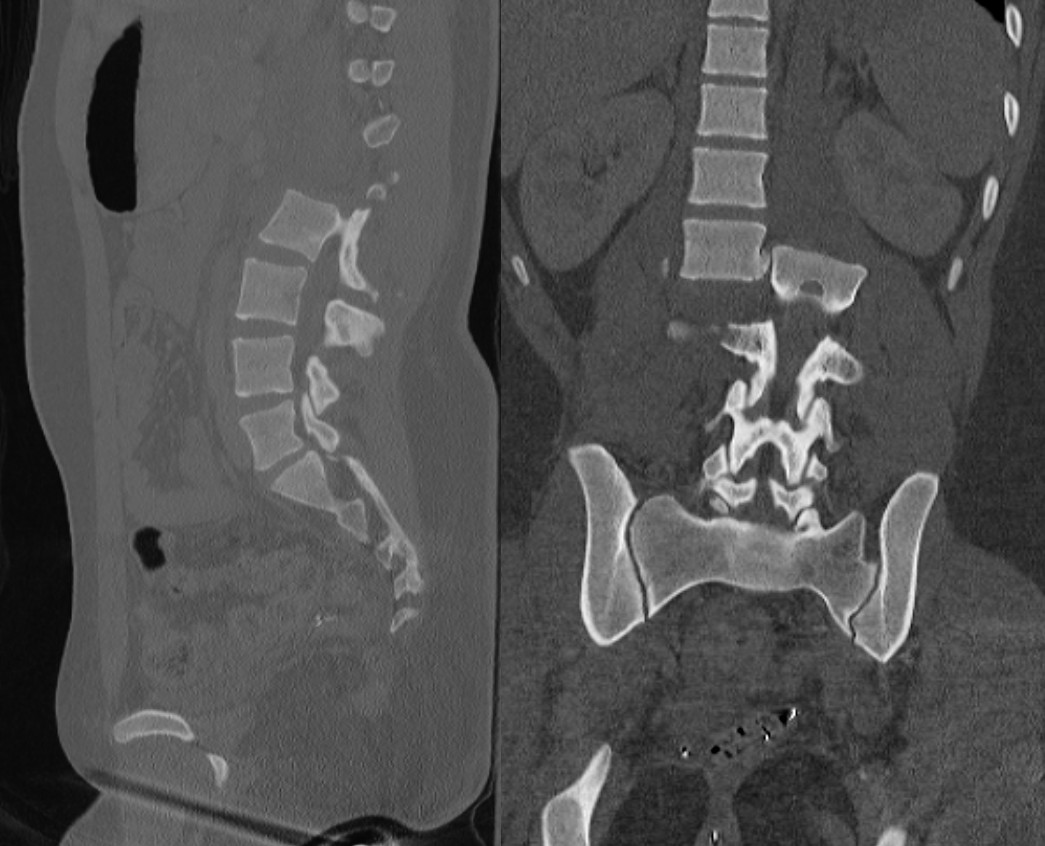

腰椎骨折

ct, mri(核磁共振)提示:第一腰椎椎体,椎板,棘突骨折并明显移位,脊髓